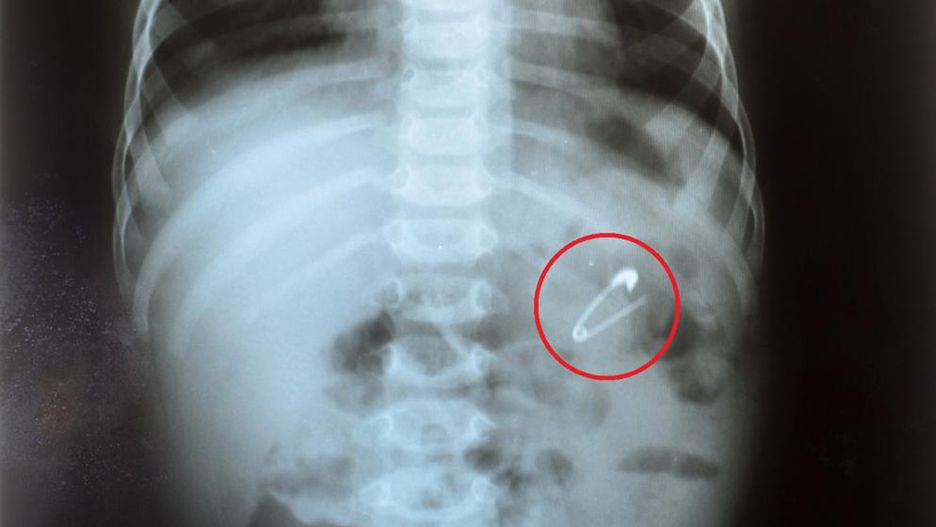

Do zdarzenia doszło 28 września 2018 roku. Na SOR w Krotoszynie (woj. wielkopolskie) przyjęty został sześciomiesięczny chłopiec. Rodzice poinformowali dyżurującą lekarkę, że ich syn połknął agrafkę.

Wykonane przez lekarkę badania potwierdziły, że w przełyku dziecka jest agrafka. Kobieta jednak odesłała rodziców z dzieckiem do innego szpitala. Nie zleciła także przewozu malucha karetką.

- Na miejscu wykonano badanie RTG przełyku i jamy brzusznej, które potwierdziło obecność w przełyku ciała obcego. Po wykonaniu tego badania pełniąca wówczas dyżur oskarżona lekarka, nie wykonując dalszej diagnostyki i nie zapoznając się z dokumentacją medyczną chłopca, poleciła rodzicom przetransportowanie chłopca do Szpitala w Ostrowie Wielkopolskim - tłumaczył Krzysztof Bukowiecki, rzecznik prasowy prokuratury regionalnej w Łodzi.

Na oddziale SOR w Ostrowie Wlkp. lekarz dyżurujący stwierdził, że agrafka utknęła w okolicy tchawicy. Zdaniem medyków stanowiła ona realne zagrożenie dla pacjenta, ponieważ podczas podróży nastąpiło dalsze jej przemieszczenie. W ocenie ostrowskich lekarzy zalecanie transportu prywatnego było nieprawidłowe.

Ze względu na wiek chłopca i lokalizację agrafki, zadecydowano o przewiezieniu dziecka do Szpitala Klinicznego nr 1 im. Marii Curie-Skłodowskiej we Wrocławiu, gdzie podczas zabiegu laparoskopem lekarze wyjęli agrafkę wczepioną w struktury przełyku maluszka.